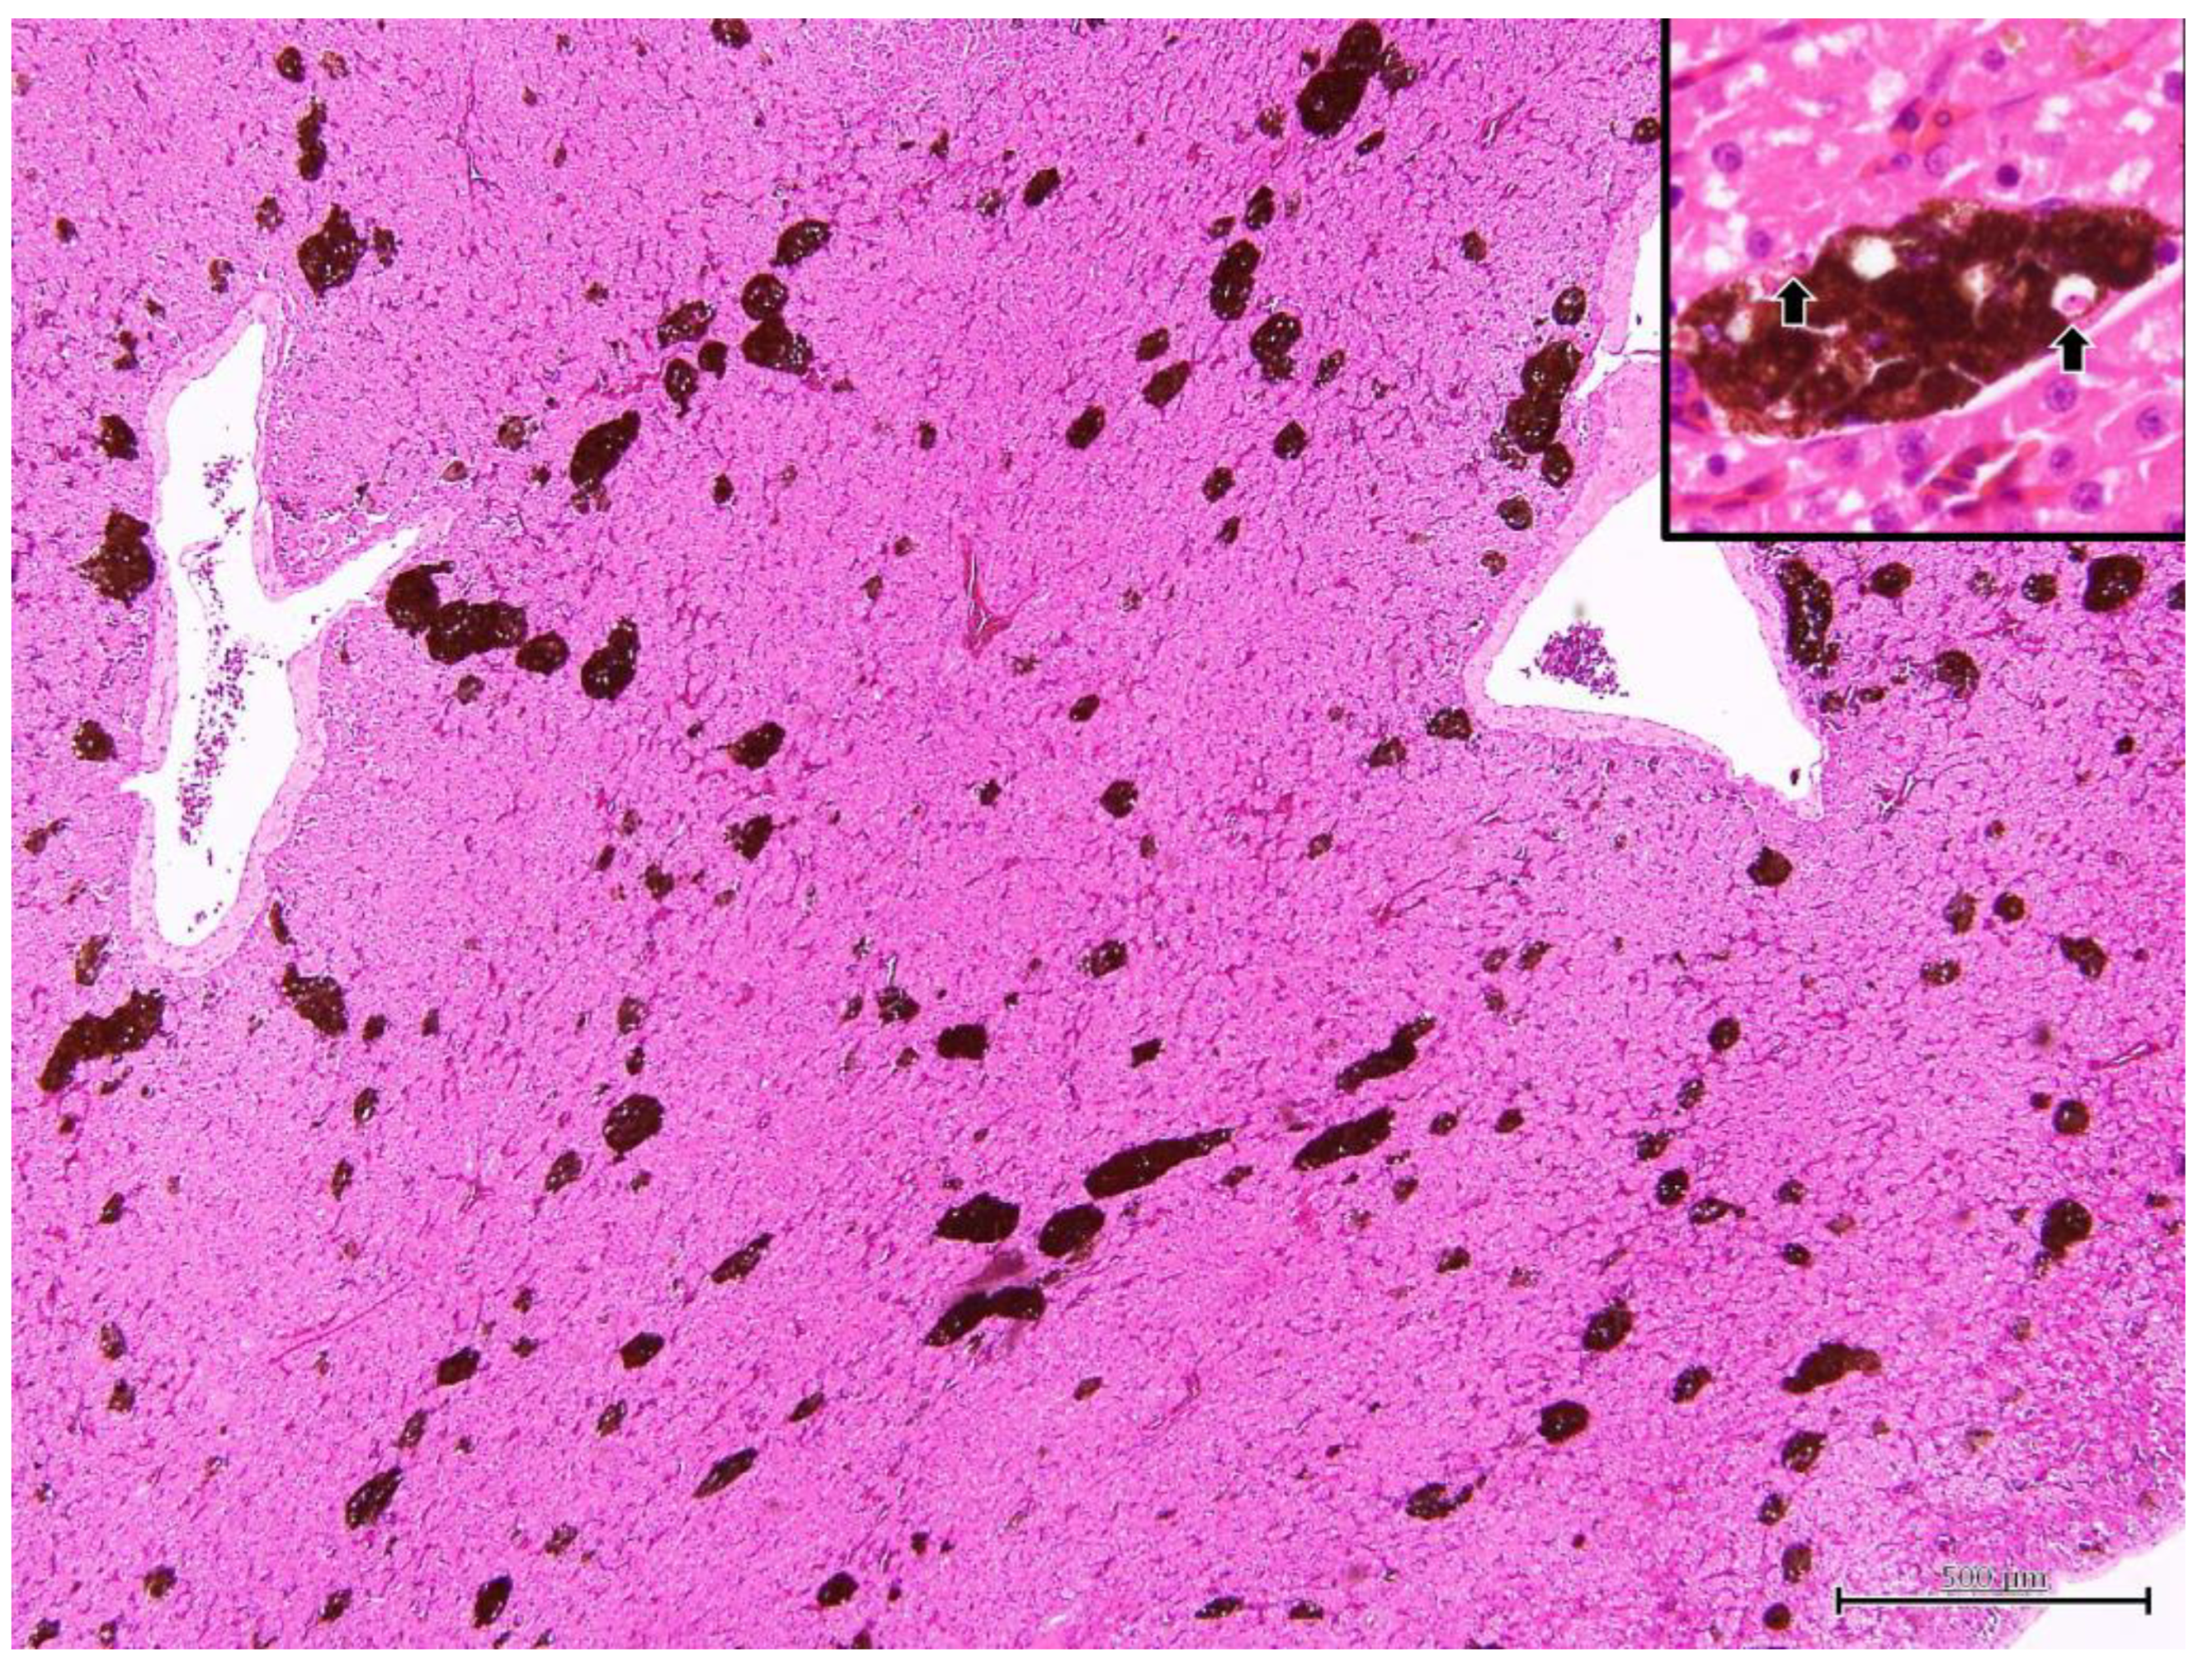

3.2. Postmortem Examination in Iguana 1